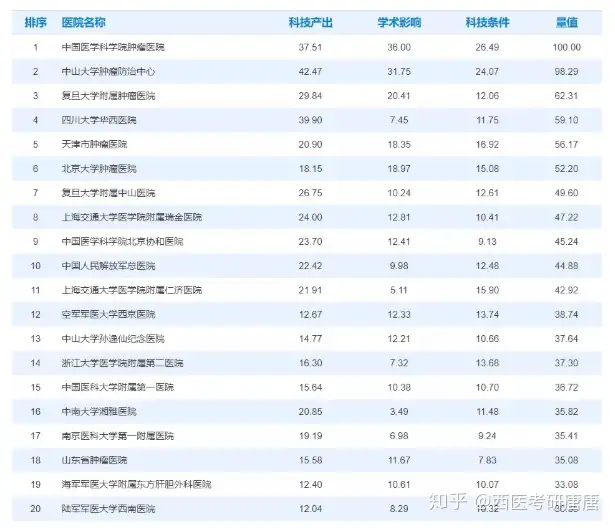

每个学校的肿瘤内科一般来说都是比较热门的,分数也比较高,所以首先还是要有个比较高的分数保证自己能进复试,同时高分也是一种优势。不过今年有些学校的肿瘤科是小年,下面会有介绍。顺便说一下,如果读肿瘤内科…